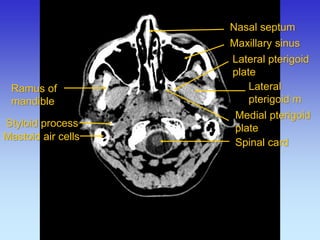

BAZA LUBANJE - CT

Ramus of mandible

Lateral pterigoid m

Lateral pterigoid plate

Medial pterigoid plate

Maxillary sinus

Nasal septum

Mastoid process

Spinal card

Styloid process

Mastoid air cells